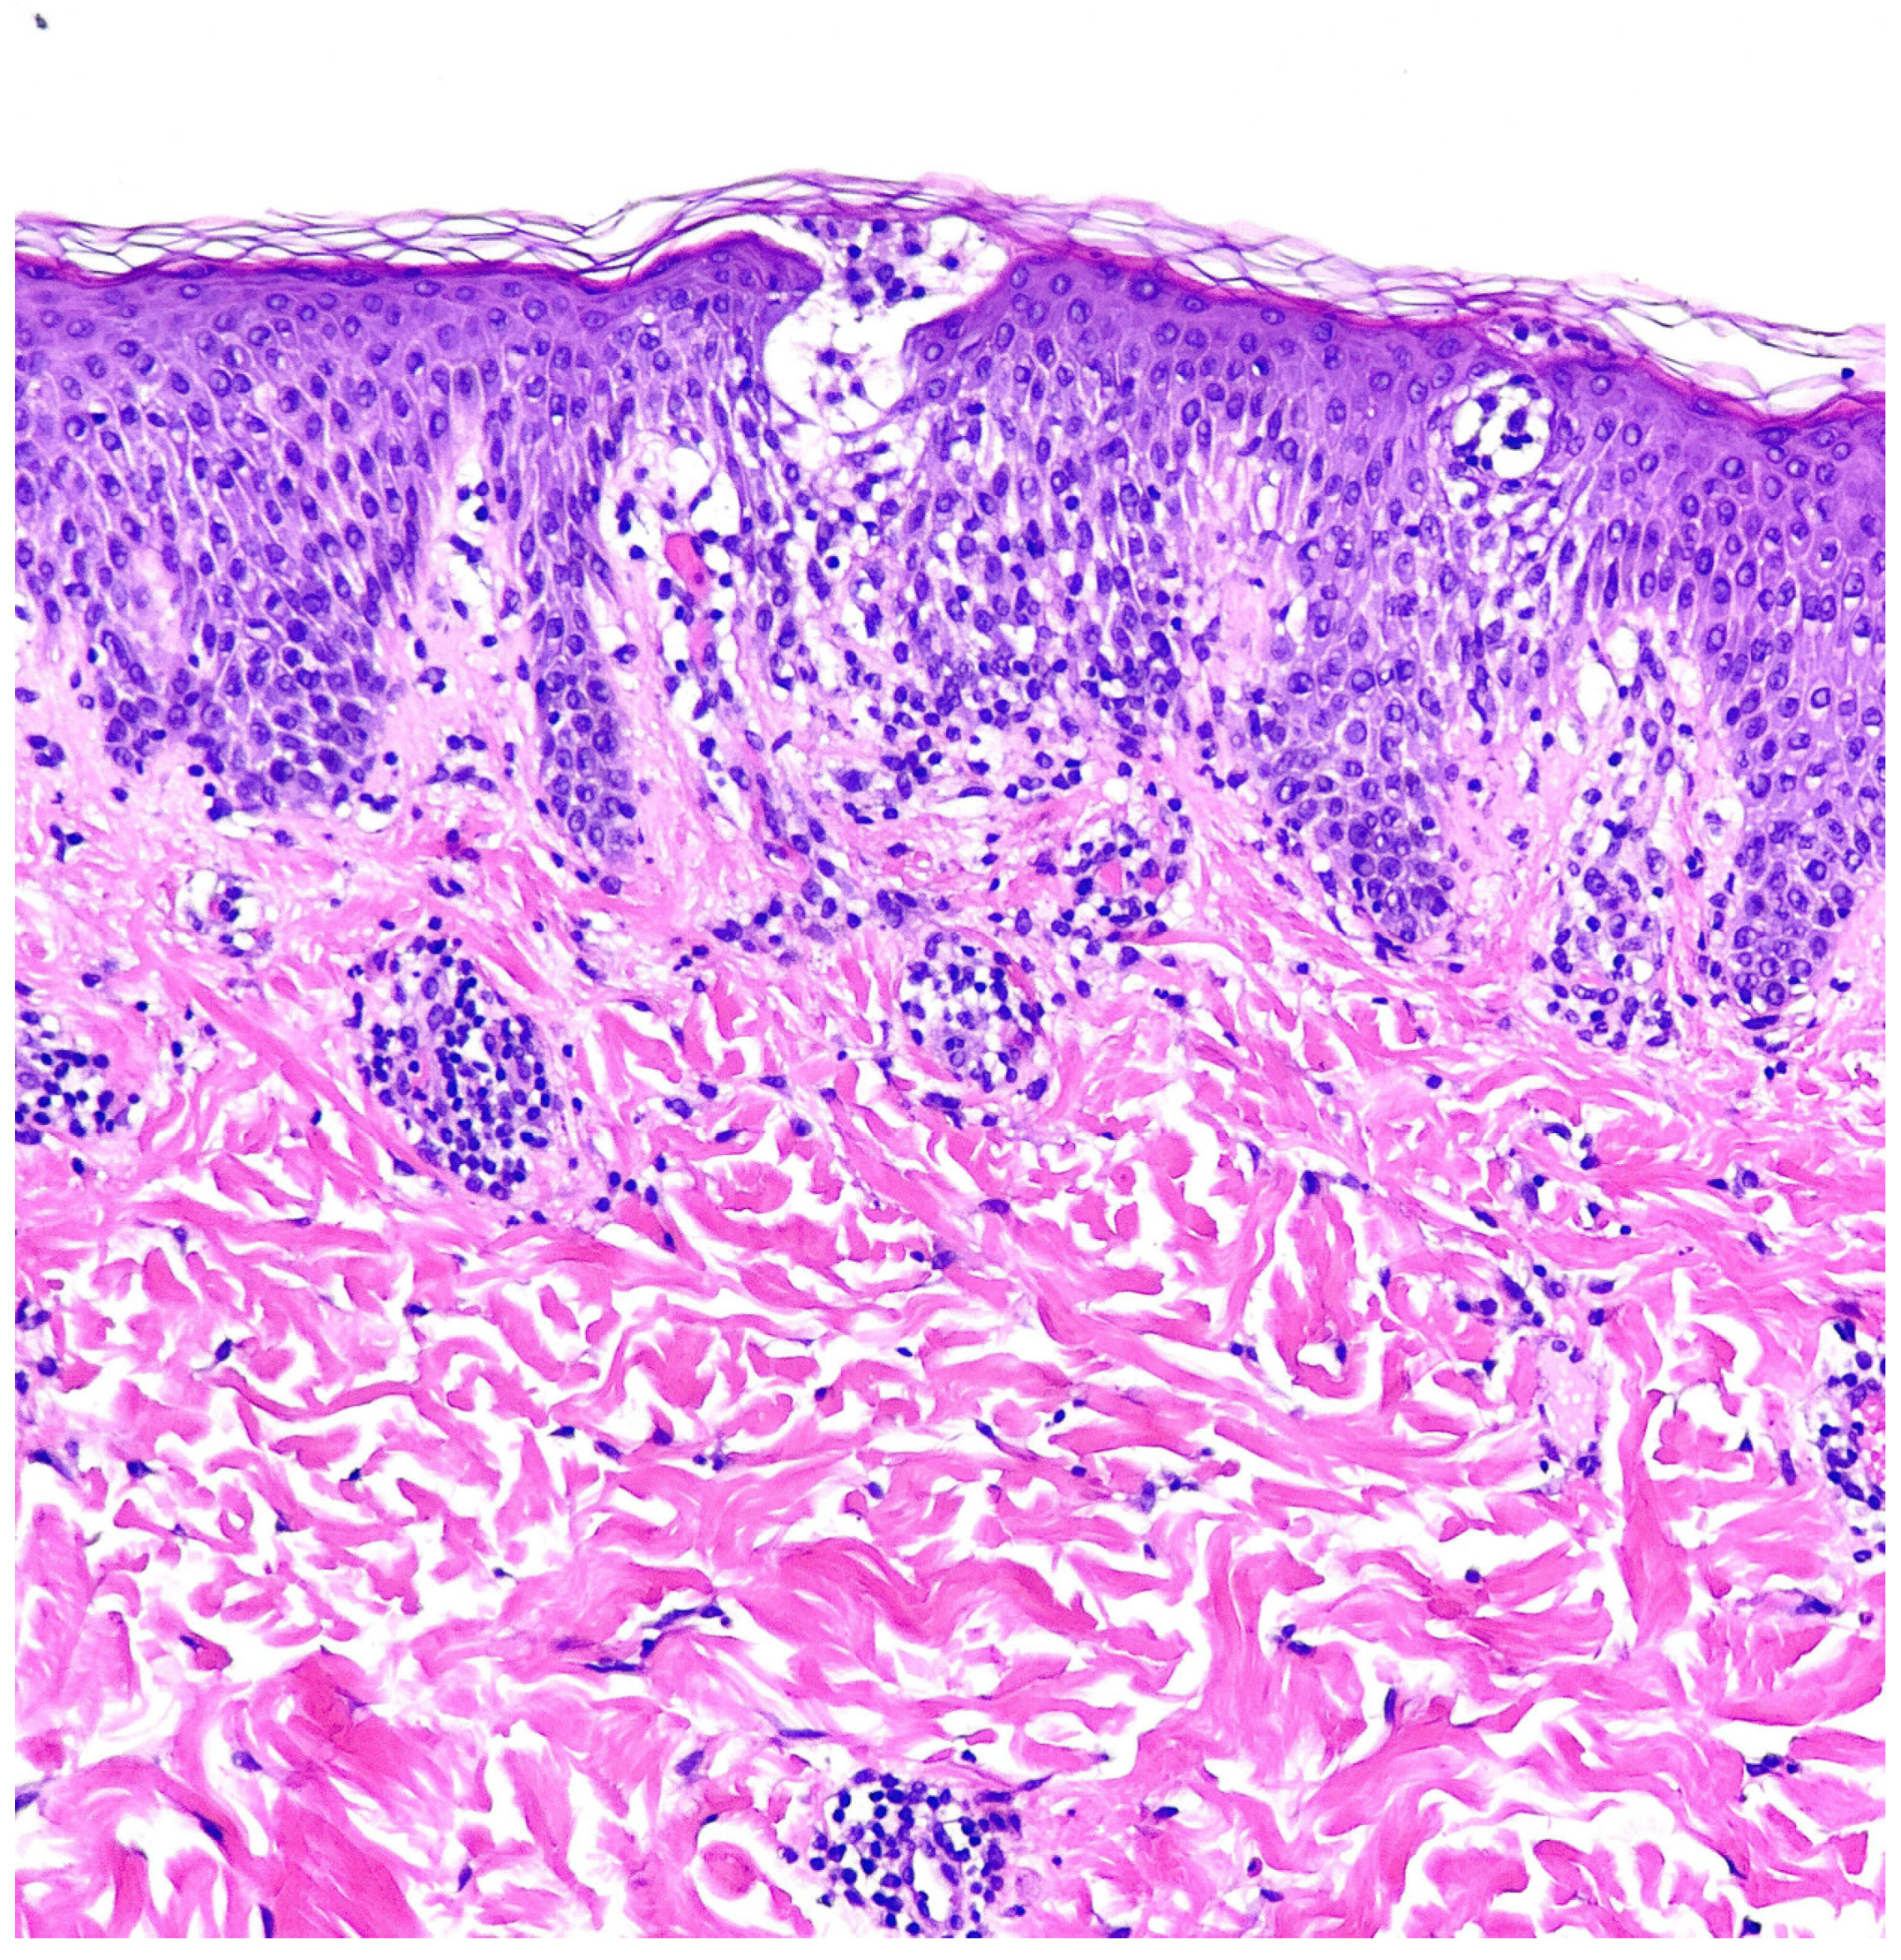

2. Case Report